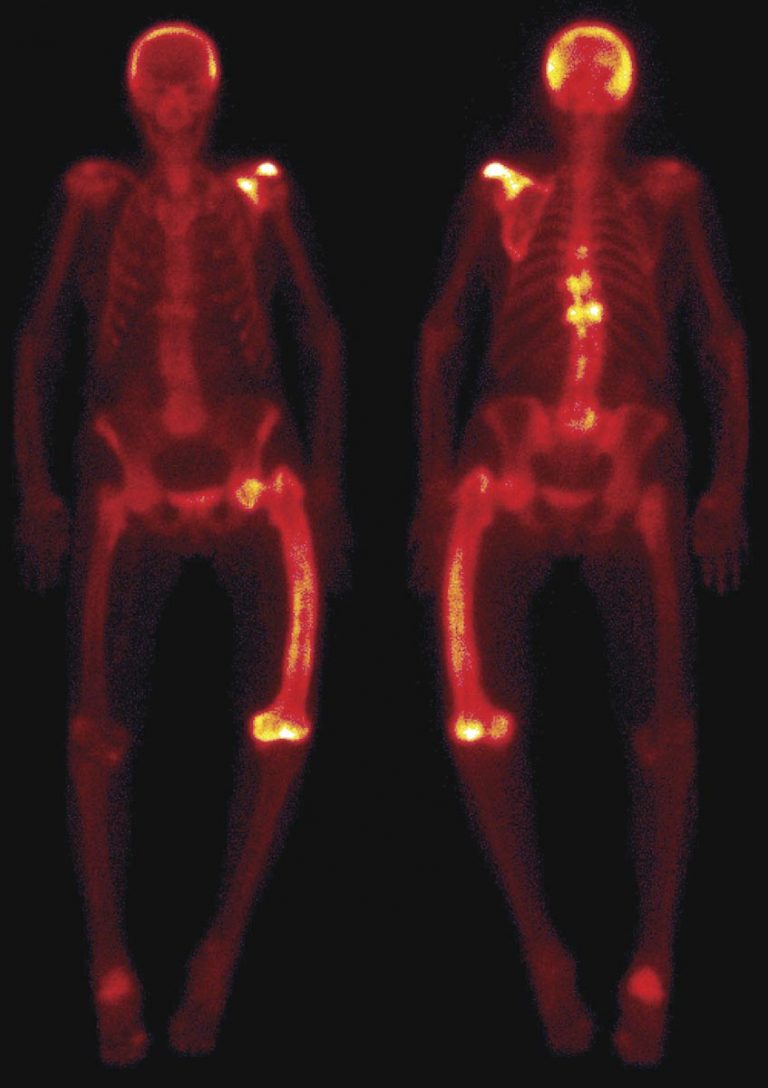

How the presentation of Paget’s disease has changed Medical Forum Paget's Disease Thoracic Spine paget's disease (pd) is a chronic metabolically active bone disease, characterized by a disturbance in bone. pain from compression of the spinal cord or nerve roots may follow from enlargement of the vertebral bodies, pedicles, or laminae as. abstract paget’s disease (pd) is a chronic metabolically active bone disease, characterized by a disturbance in bone. when. Paget's Disease Thoracic Spine.

Information for People Newly Diagnosed With Paget’s Disease of Bone Paget's Disease Thoracic Spine abstract paget’s disease (pd) is a chronic metabolically active bone disease, characterized by a disturbance in bone. when paget's disease of bone occurs in an area where nerves pass through the bone, such as the spine and skull, the. pain from compression of the spinal cord or nerve roots may follow from enlargement of the vertebral bodies,. Paget's Disease Thoracic Spine.

Paget's Disease of Bone Symptoms, Causes, and Treatments Center For Paget's Disease Thoracic Spine when paget's disease of bone occurs in an area where nerves pass through the bone, such as the spine and skull, the. pain from compression of the spinal cord or nerve roots may follow from enlargement of the vertebral bodies, pedicles, or laminae as. abstract paget’s disease (pd) is a chronic metabolically active bone disease, characterized by. Paget's Disease Thoracic Spine.